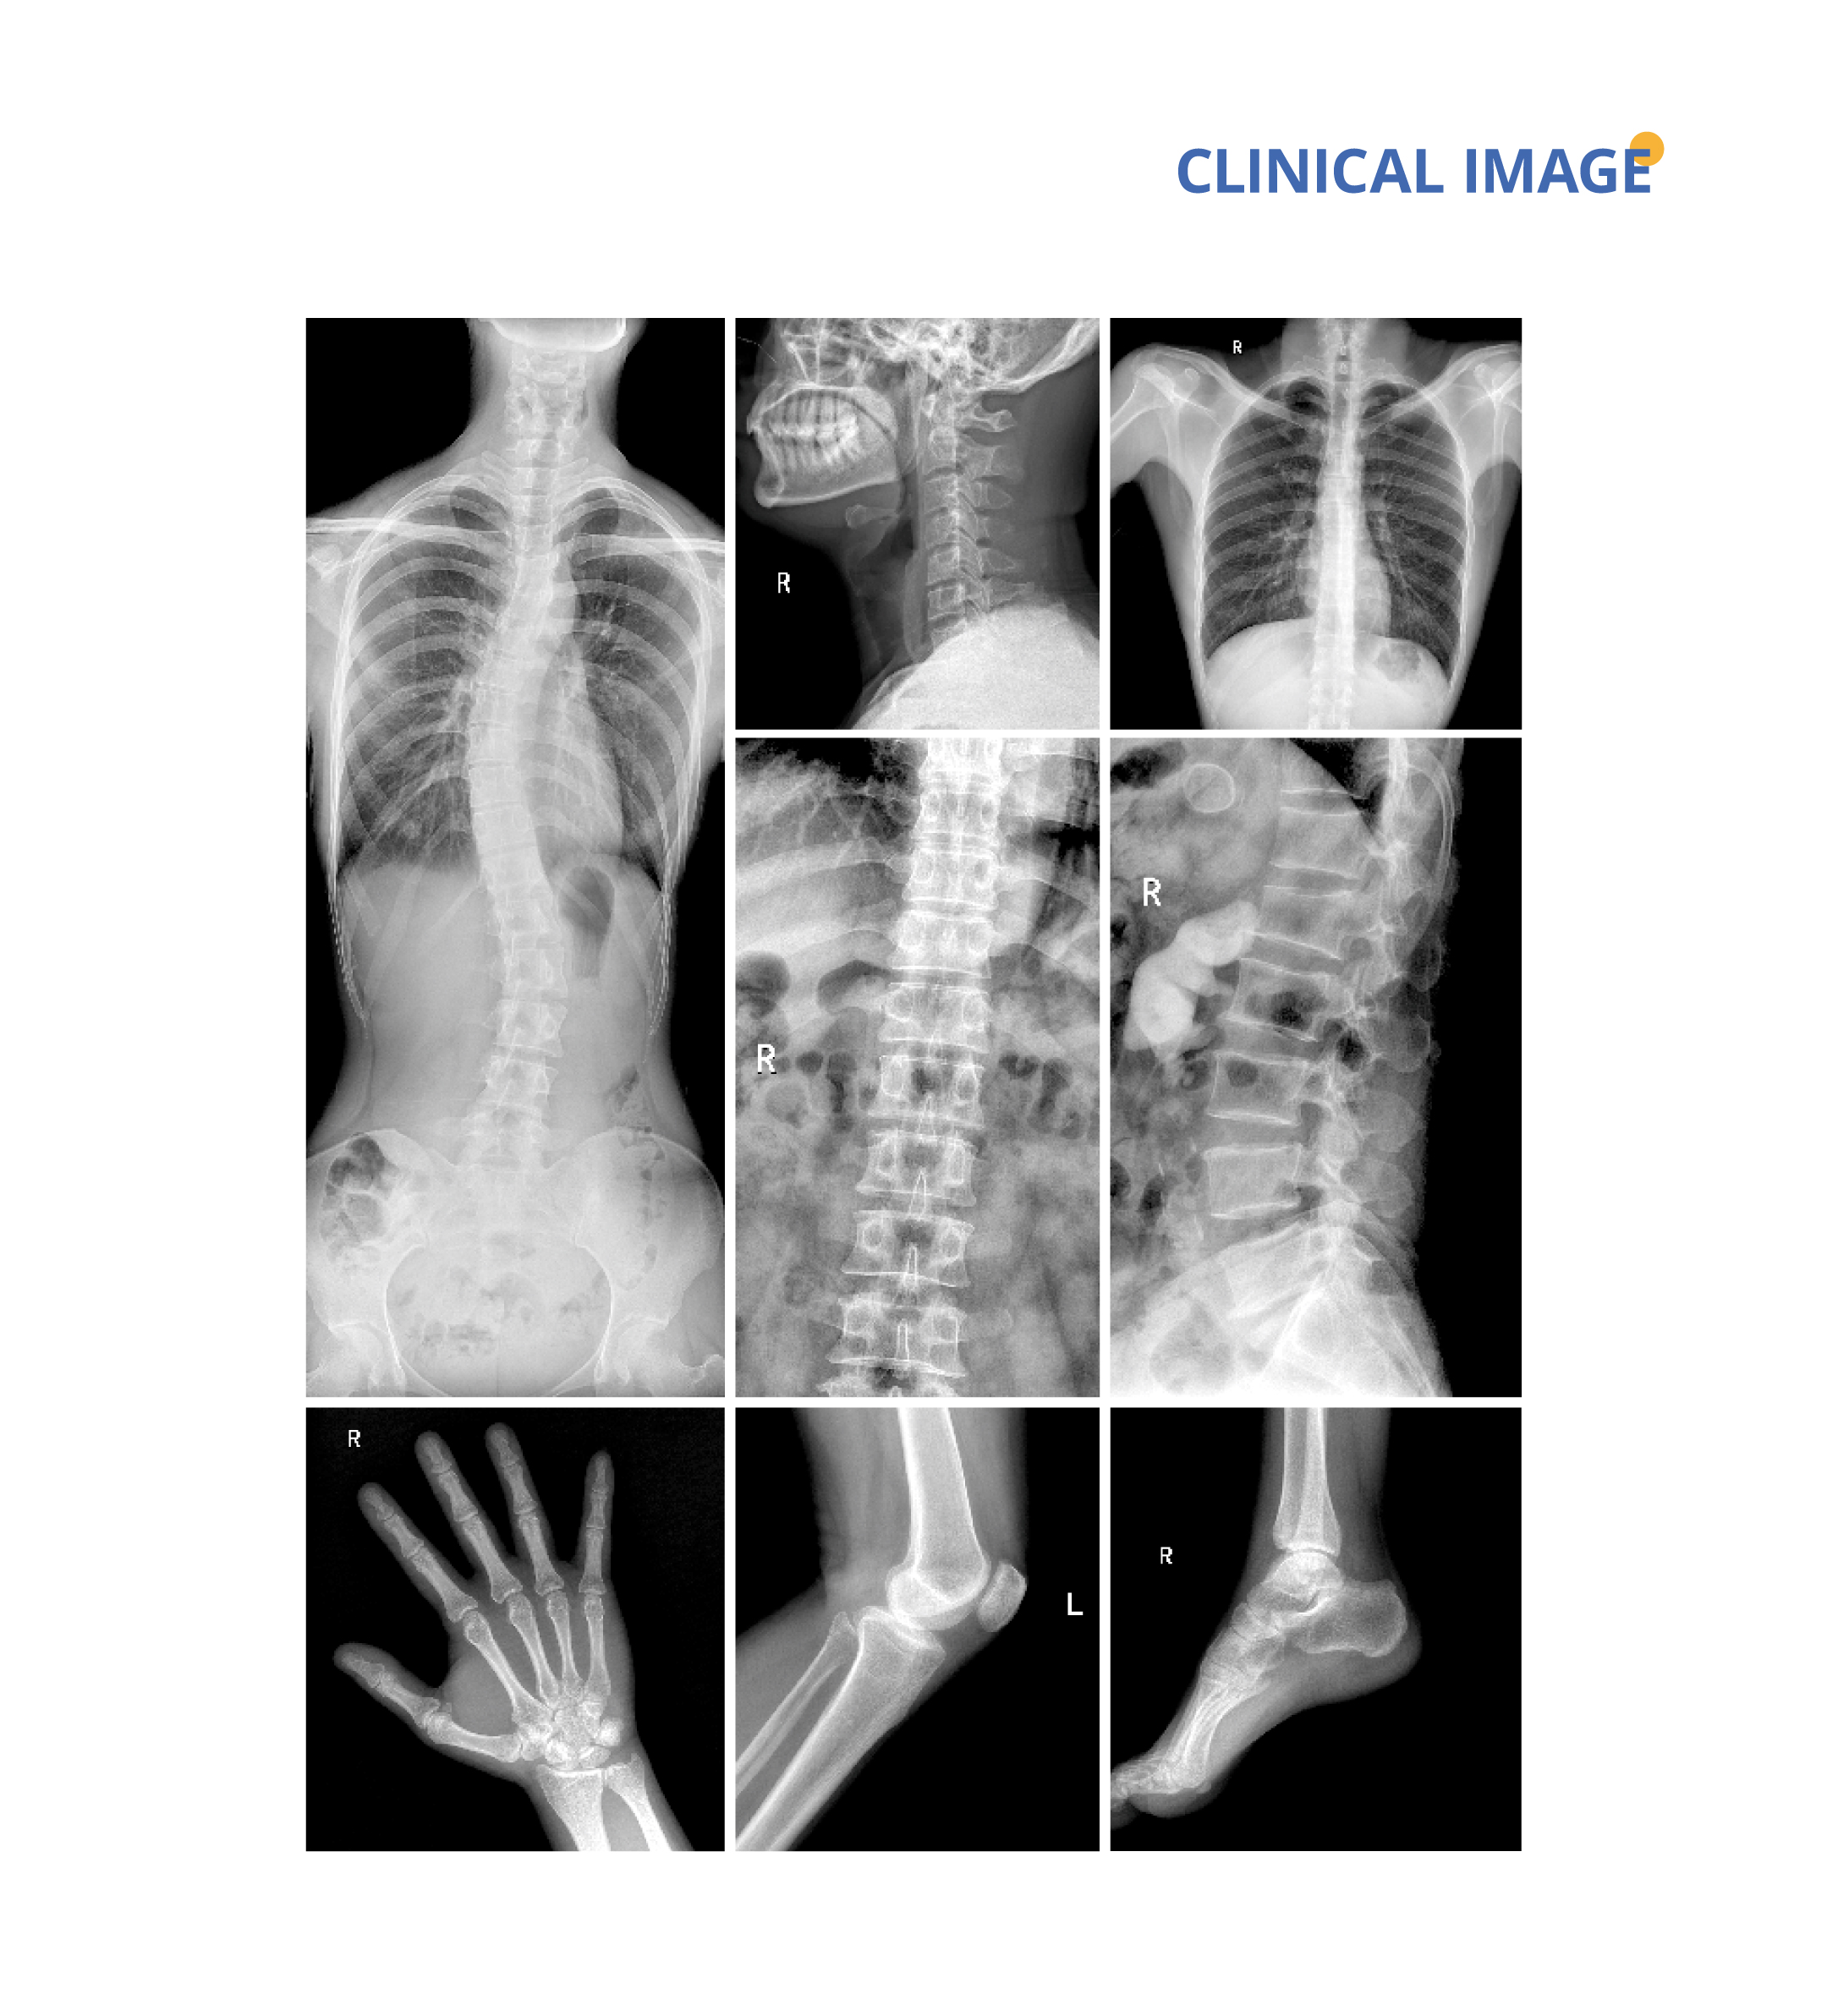

The dynamic detector technology provides visualization conditions for clinical examinations, and realizes fast and high-definition spot-film, and accurate diagnosis.